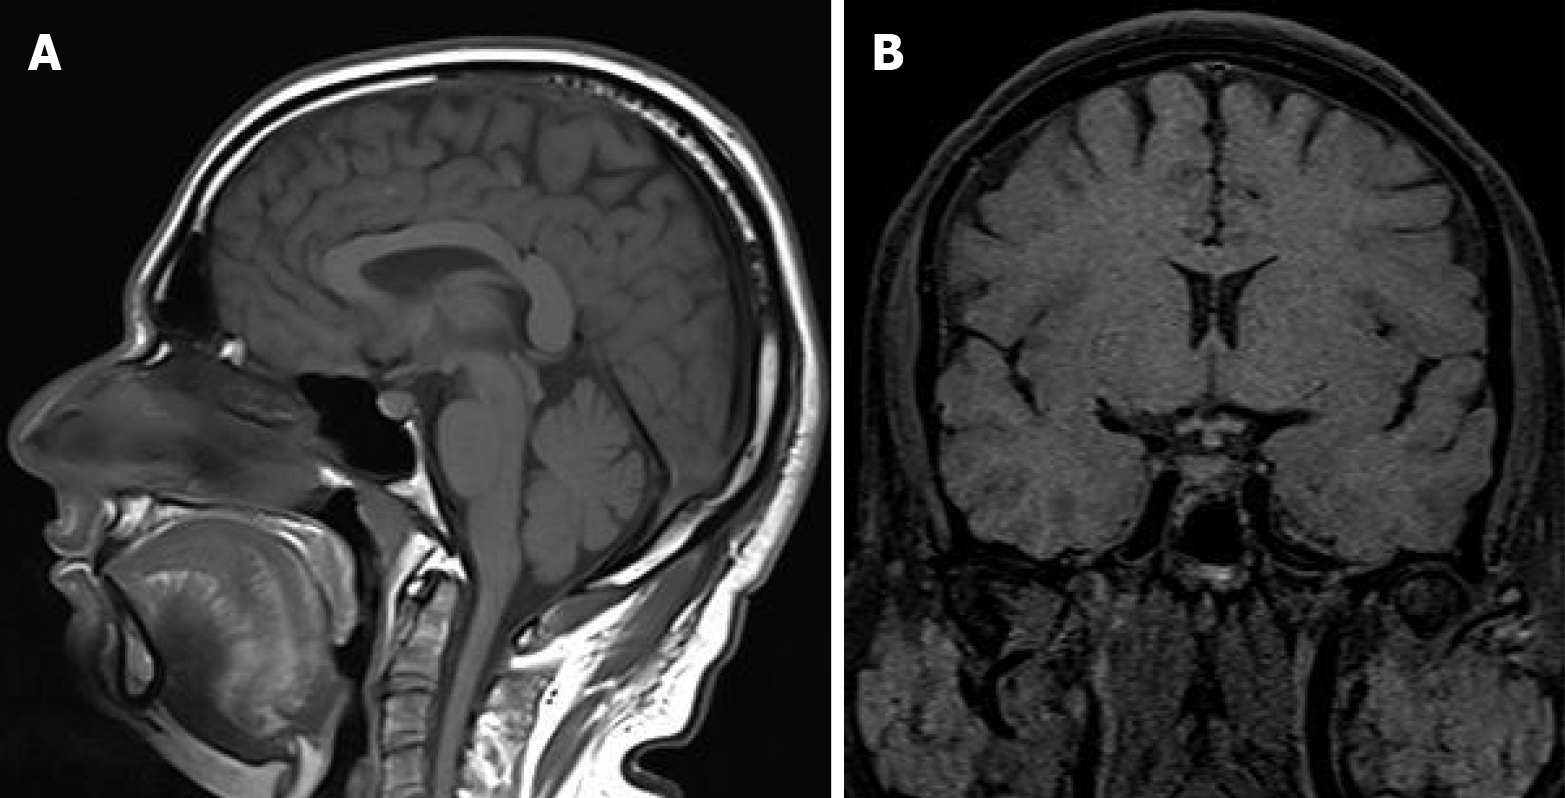

Figure 2 Sagittal view of magnetic resonance imaging brain.

A: Sagittal view of magnetic resonance imaging (MRI) brain showing absent pituitary shadow and thickened stalk; B: Coronal view of MRI brain showing absent pituitary shadow and thickened stalk.